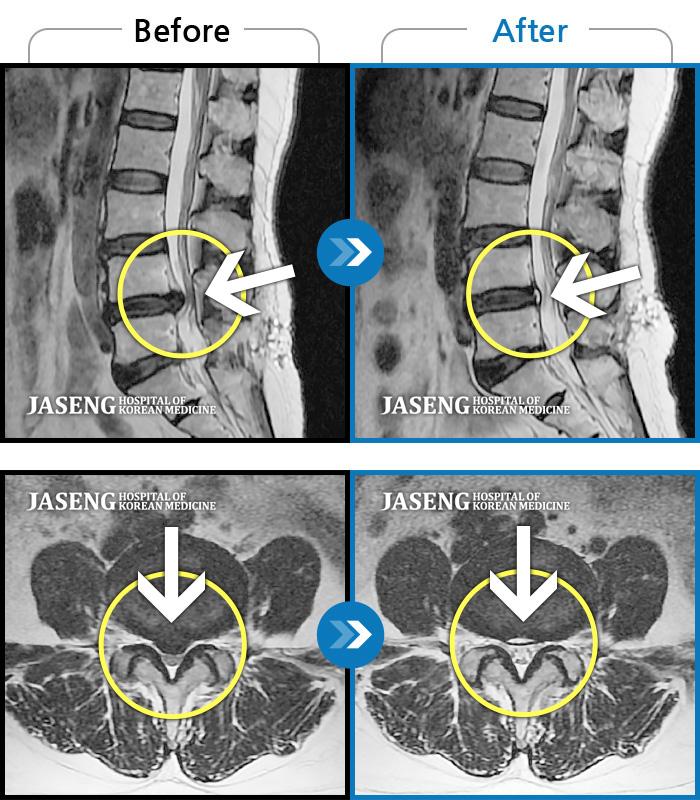

60건의 MRI 전후 사진으로 터진 디스크 흡수 사례를 확인하세요.

처음 내원시 목에서 등으로 이어지는 통증 및 우측 팔 저림 증상이 심했고, 약간의 근력저하도 동반되어 일상생활이 어려운 상태였습니다. |

[인천] 24.04.06~24.11.16

※ 환자분에게 사전 동의를 받아 동일 조건에서 촬영되었으며, 개인에 따라 치료 후 부작용이 발생할 수도 있으니 사전에 의료진과 상담 후 치료를 진행하시기 바랍니다.